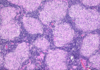

features of macrophages

- big cells with a large cytoplasm - abundant foamy cytoplasm - slipper shaped nucleus - can look like a cancer cell

primary role of maxcrophage

phagocytosis - removal of pathogens/ necrosis/ debris - antigen presentation to immune system

secondary role of macrophages

- Also produce inflammatory mediators- controls and regulates inflammatory response